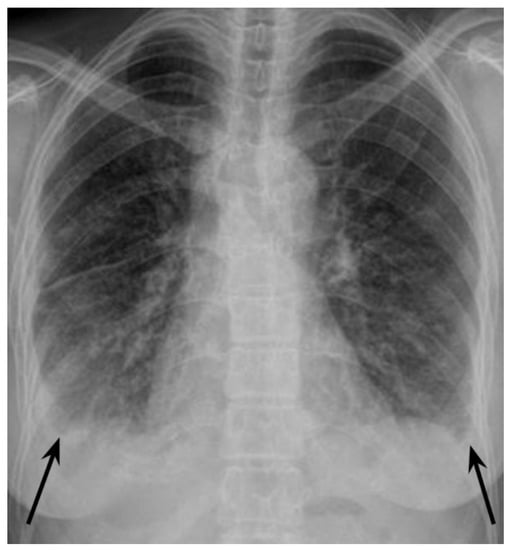

Figure 1. Infection with human immunodeficiency virus (HIV) is the strongest known risk factor for active tuberculosis (TB), and the risk of developing active TB in people living with HIV (PLWH) is 15–22 times higher than in people without HIV [1]. Active TB may develop at any stage of HIV infection, but the risk correlates negatively with CD4+ cells count. TB is the leading cause of morbidity, hospitalisations, and mortality in PLWH [1]. There were 214,000 deaths due to TB among HIV-positive people in 2020 worldwide, which accounted for 31.5% of all HIV-related deaths [1,2]. Therefore, it is recommended to screen for TB in HIV-positive patients, and for HIV infection in newly diagnosed TB patients [3,4,5]. Around 16% of all PLWH do not know that they are infected with HIV [1], and about 25% of incident HIV patients present to care with advanced disease [3]. Immunosuppression caused by HIV infection affects clinical and radiologic presentation of TB. Atypical TB presentation is often observed in the late stages of HIV infection [6,7,8,9]. Such atypical TB presentation in a person with HIV infection not yet diagnosed, may be challenging, as described below. A 42-year-old woman of Indian origin was referred to a respiratory medicine department after her chest X-ray (Figure 1) revealed nodular opacifications in the lungs and bilateral pleural effusion (arrows). The patient had a 4-month history of unspecific chest and feet pains, mild dry cough, fatigue, reduced appetite, and body weight loss of 6 kg. She denied dyspnoea, sputum expectoration, haemoptysis, night sweats, or fever. On admission to the hospital, she was in good condition, her vital signs were normal, BMI was 19.2. There was no palpable peripheral lymphadenopathy or oedema; the vesicular breathing sound was reduced bibasiliary on chest auscultation. Blood tests showed elevated CRP—109.4 (N:<5) mg/L and ERS—120 (N: < 12), normal procalcitonin, normal leukocyte and neutrophil counts, decreased lymphocyte count—0.84 × 103 (N:1.18 × 103–3.74 × 103) cells/mm3.